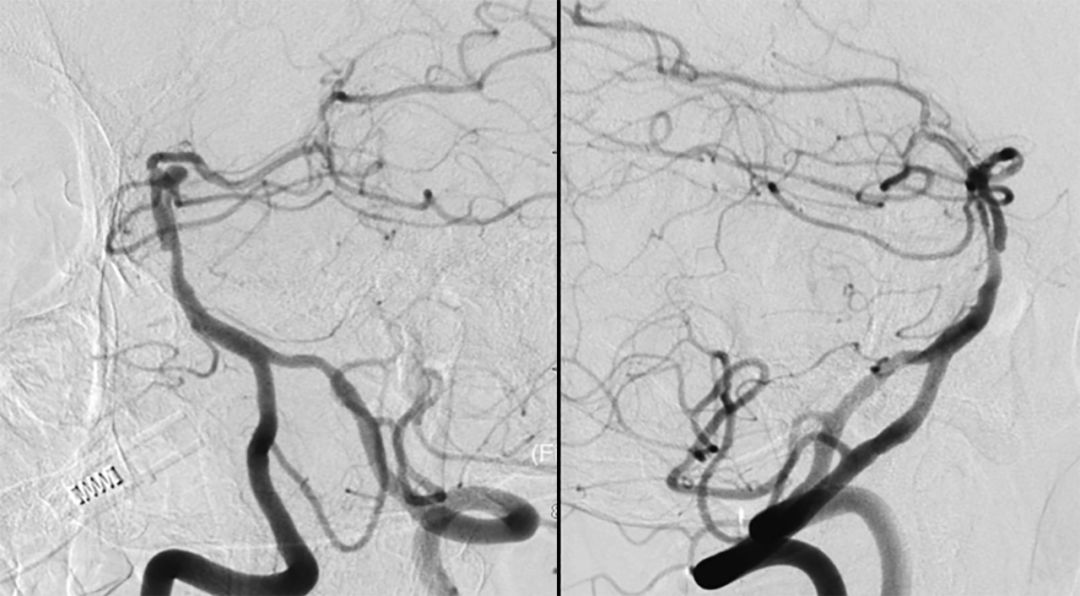

全脑血管造影(本院,2019-8-1 ):基底动脉顶端夹层或者开窗,左侧小脑上动脉瘤(图4)。

图4

2. 将Echelon-10微导管置入基底动脉较粗的管腔中进行微量造影(正位、侧位)(图6):左侧大脑后动脉显影。

3. 再将Echelon-10微导管置入基底动脉较细的管腔进行微量造影(正位、侧位)(图7):双侧大脑后动脉及左侧小脑上动脉显影,可见动脉瘤位于左侧小脑上动脉。

4. 最后将Echelon-10微导管置入基底动脉中下段进行微量造影:基底动脉2个管腔、 双侧大脑后动脉显影、小脑上动脉均可显影(图8)。

基底动脉进行三维血管重建:基底动脉有较粗和较细的2个管腔,左侧小脑上动脉瘤大小约2.3*2.1 mm(图9)。

进行上述三次微量造影均可见双侧大脑后动脉显影,以及结合基底动脉三维重建图像,故判断基底动脉属于开窗,而非夹层。由于载瘤动脉较细,拟行单微管动脉瘤栓塞术。

1. 基底动脉顶端开窗或夹层都十分少见,如为动脉夹层,首先治疗夹层将有利于患者的恢复;如为开窗畸形,要确认该动脉瘤起自哪一真腔。患者术前行高分辨磁共振仍无法确认。因此,我们用微导管分别进入基底动脉的2个管腔进行微量造影,如果2个管腔造影均可使大脑后动脉显影,则说明2个管腔均是真腔,为基底动脉开窗;如果有1个管腔无法使大脑后动脉显影,则该管腔为假腔(夹层)。